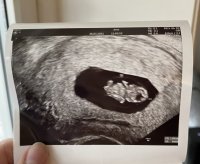

Vi kunne ikke se noe på mandag så her går det rett vei mener de. Hcg øker som det skal og hadde 4100 igår, hvordan er dine? Jeg har time igjen neste uke jeg og, antar han bare er slow starter som broren varAkkurat slik var det hos meg også på mandag. Var også 5+5 da. Fikk UL på grunn av blødninger. Og den så ganske lik ut som hos deg. En fostersekk i livmoren, men ikke så mye mer å se.

han tok nok flere målinger som i gjennomsnitt gav 6+3, mens denne ene målingen kanskje viste tilsvarende 6+6. I de fleste tilfeller er det uansett menstermin som "teller" frem til ordinær UL